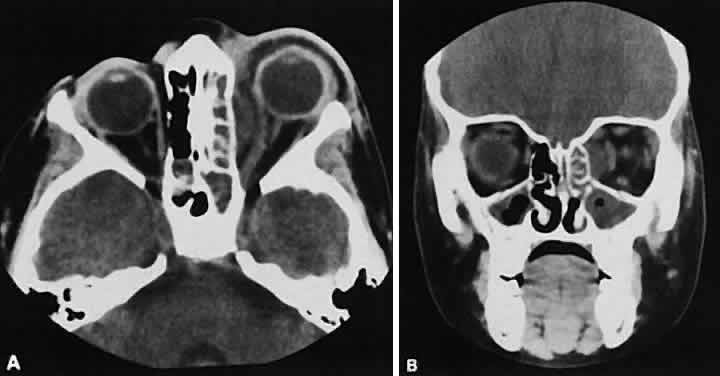

Fig. 6. Nonspecific inflammatory dacryoadenitis. An isodense enlargement of the lacrimal gland is noted on axial (A) and coronal (B) views. Note the similarity to Figure 18.

Fig. 18. Axial (A) and coronal (B) views of lacrimal gland lymphoma. There is homogenous enhancement of the enlarged lacrimal gland. Compared with Fig. 6, there is no difference.